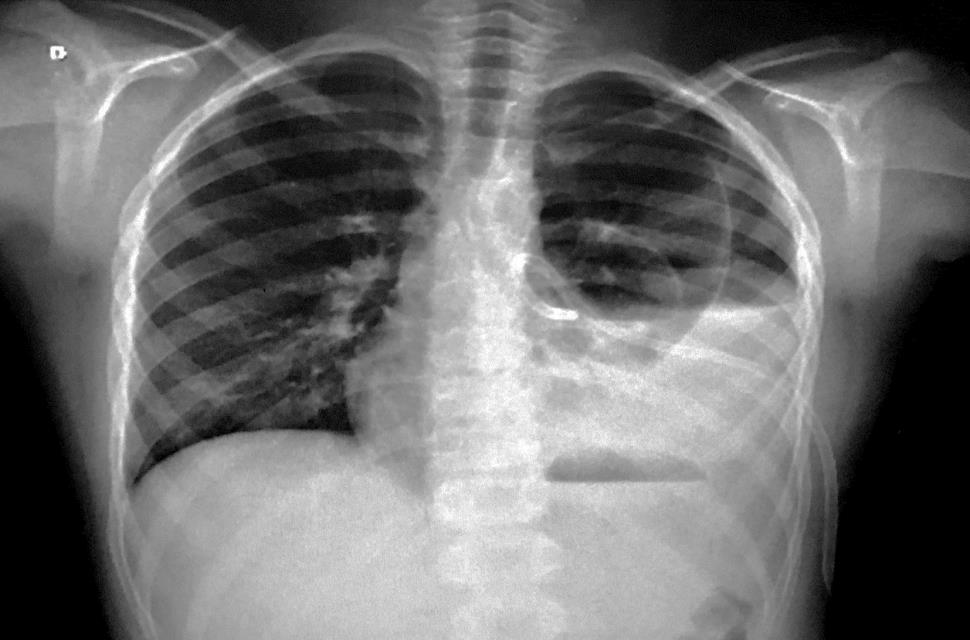

Considere a radiografia de tórax abaixo.

O diagnóstico mais provável é: